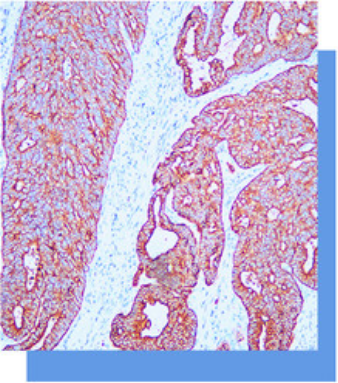

细胞角蛋白8抗体试剂

细胞角蛋白8(CK8)属低分子量B型细胞角蛋

白,常与细胞角蛋白18结合在一起。主要标记非

鳞状上皮,因此主要用于腺癌和导管癌的诊断,

鳞癌- -般不表达CK8。有报道称肝细胞癌主要表

达CK8和CK18。